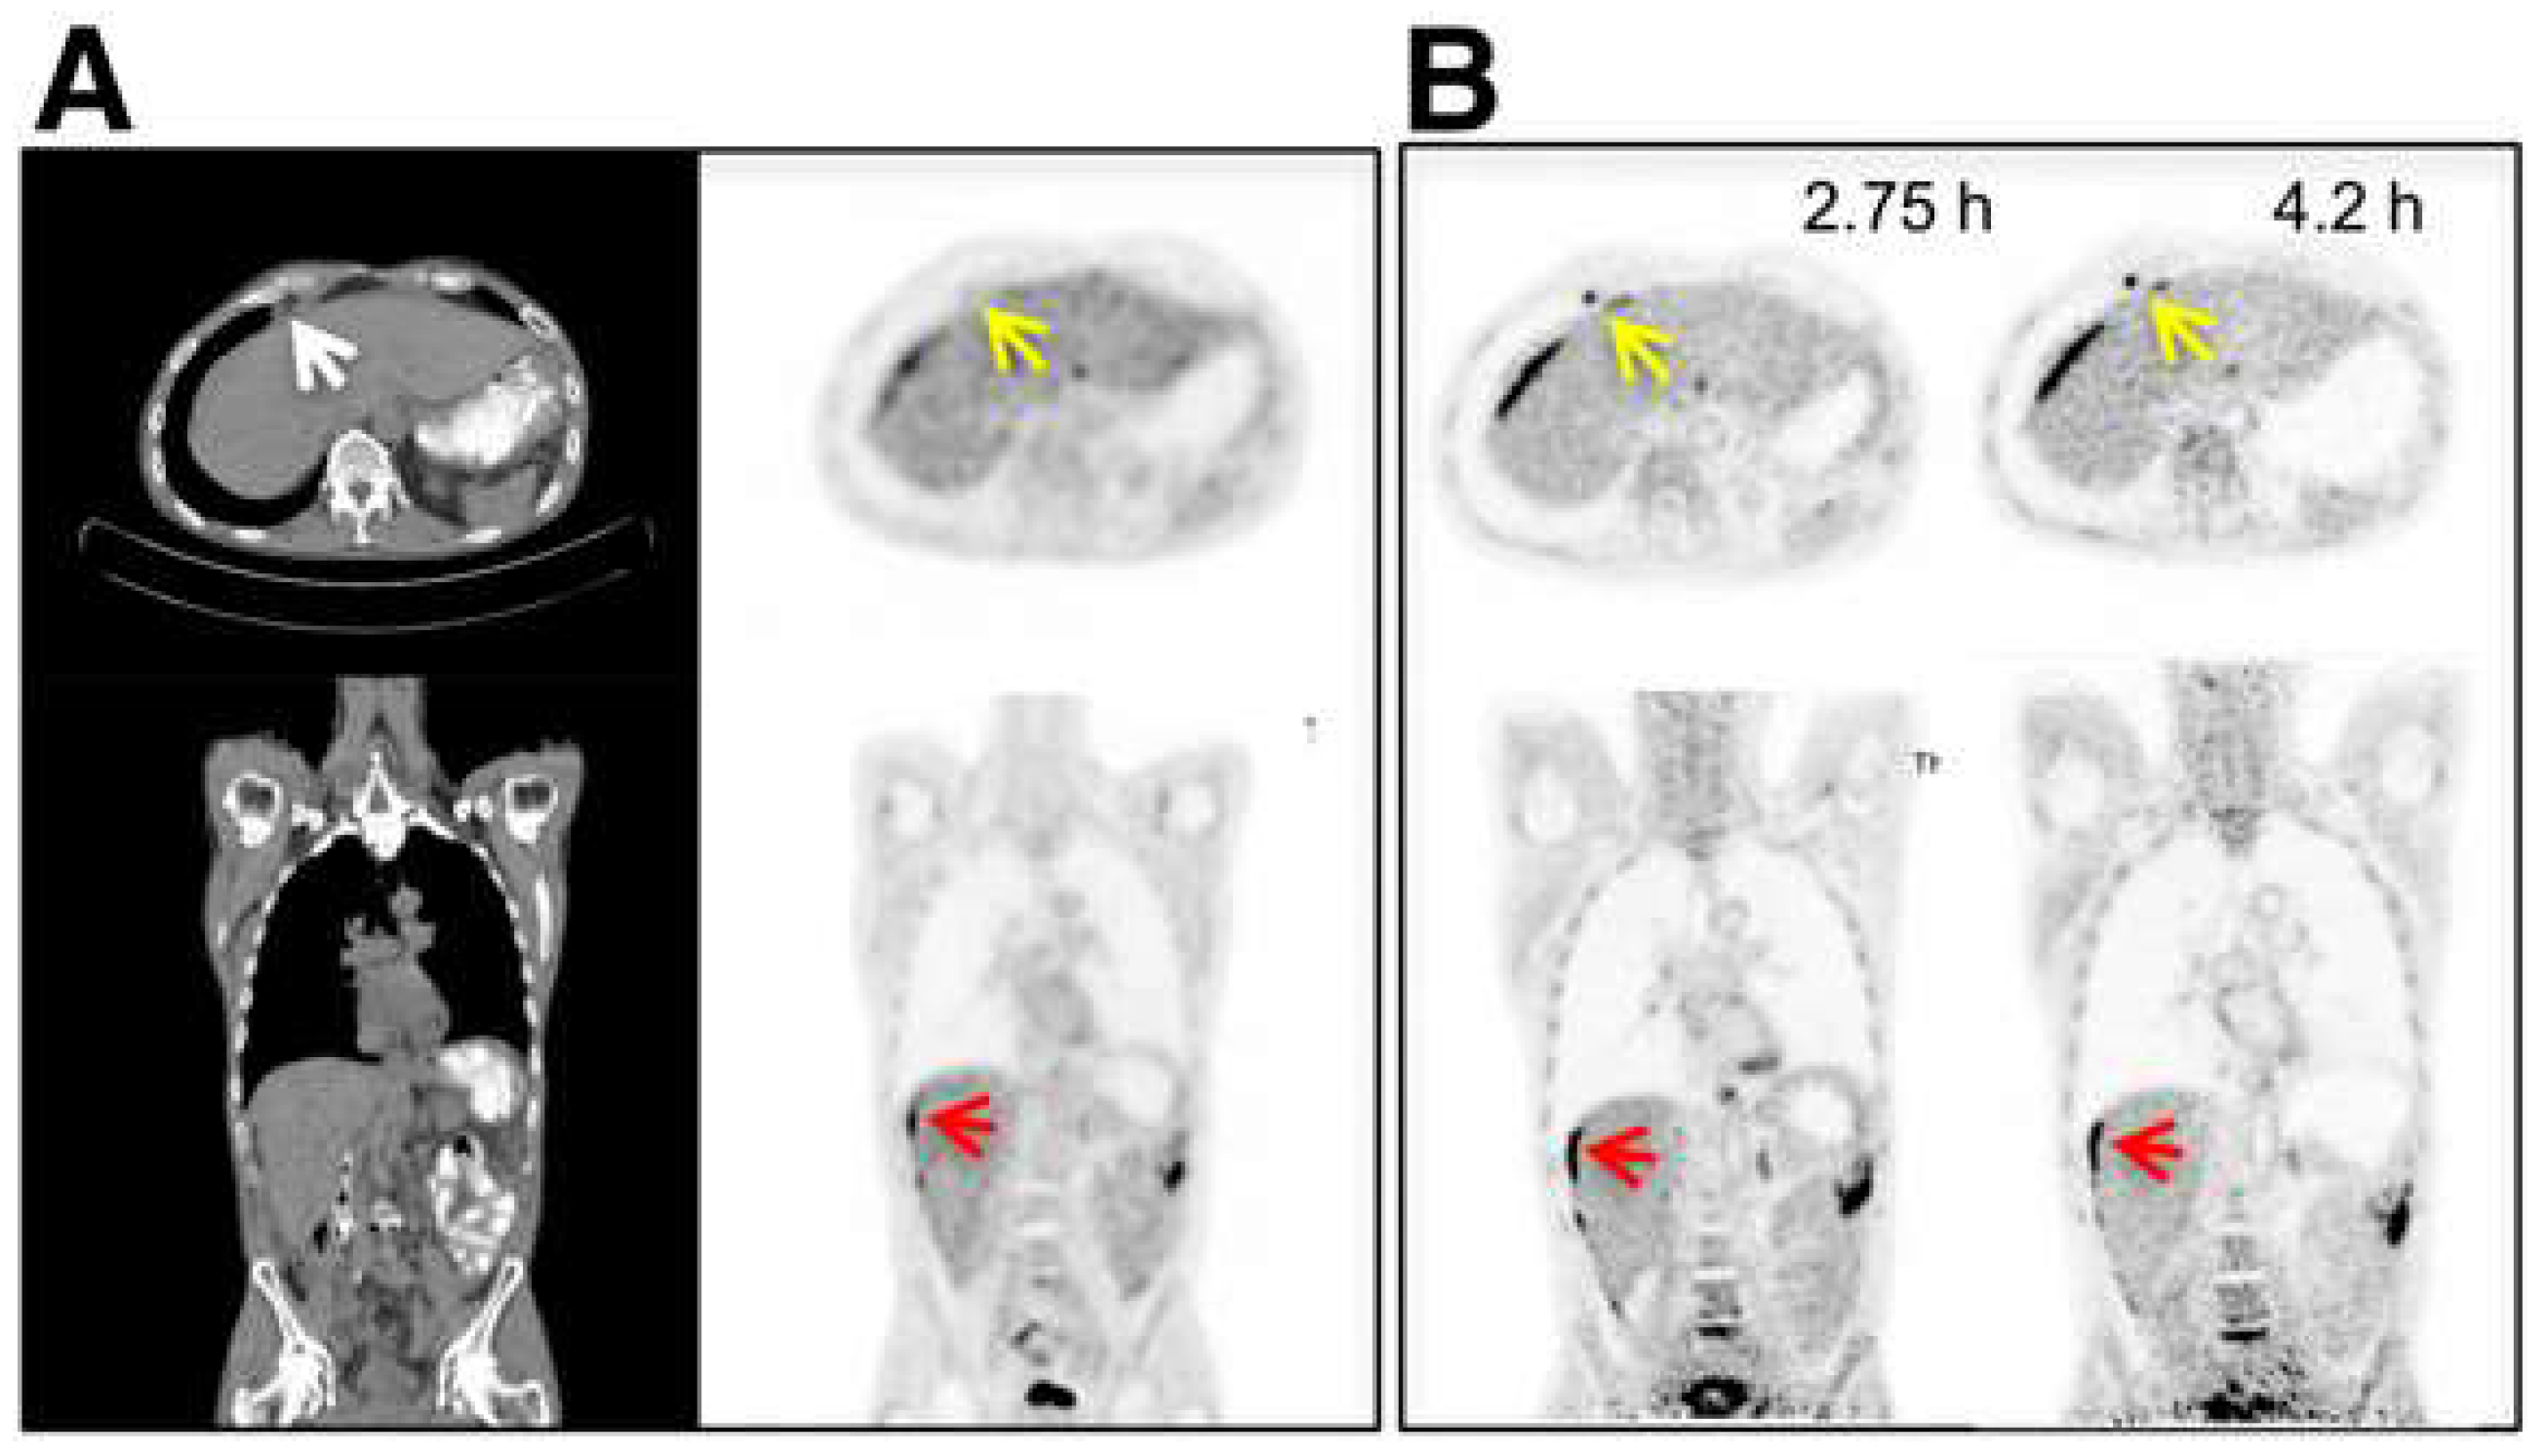

4. Longitudinal and Delayed Imaging

- Zhuang, H.; Pourdehnad, M.; Lambright, E.S.; Yamamoto, A.J.; Lanuti, M.; Li, P.; Mozley, P.D.; Rossman, M.D.; Albelda, S.M.; Alavi, A. Dual time point 18F-FDG PET imaging for differentiating malignant from inflammatory processes. J. Nucl. Med. 2001, 42, 1412–1417. [Google Scholar]

- Houshmand, S.; Salavati, A.; Segtnan, E.A.; Grupe, P.; Hoilund-Carlsen, P.F.; Alavi, A. Dual-time-point Imaging and Delayed-time-point Fluorodeoxyglucose-PET/Computed Tomography Imaging in Various Clinical Settings. PET Clin. 2016, 11, 65–84. [Google Scholar] [CrossRef]

- Soffers, F.; Helsen, N.; Van den Wyngaert, T.; Carp, L.; Hoekstra, O.S.; Goethals, L.; Martens, M.; Deben, K.; Spaepen, K.; De Bree, R.; et al. Dual time point imaging in locally advanced head and neck cancer to assess residual nodal disease after chemoradiotherapy. EJNMMI Res. 2022, 12, 34. [Google Scholar] [CrossRef]